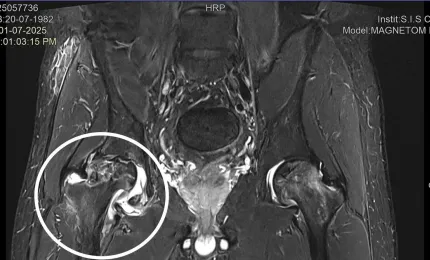

Nhiễm trùng máu vì 'cấy chỉ' chữa đau lưng

TPO - Một nam bệnh nhân 61 tuổi, trú tại Phú Thọ, được chuyển khẩn cấp đến Khoa Da liễu - Bỏng, Bệnh viện Bạch Mai tr